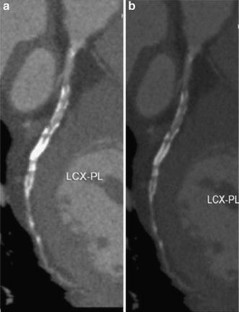

Fig. 2